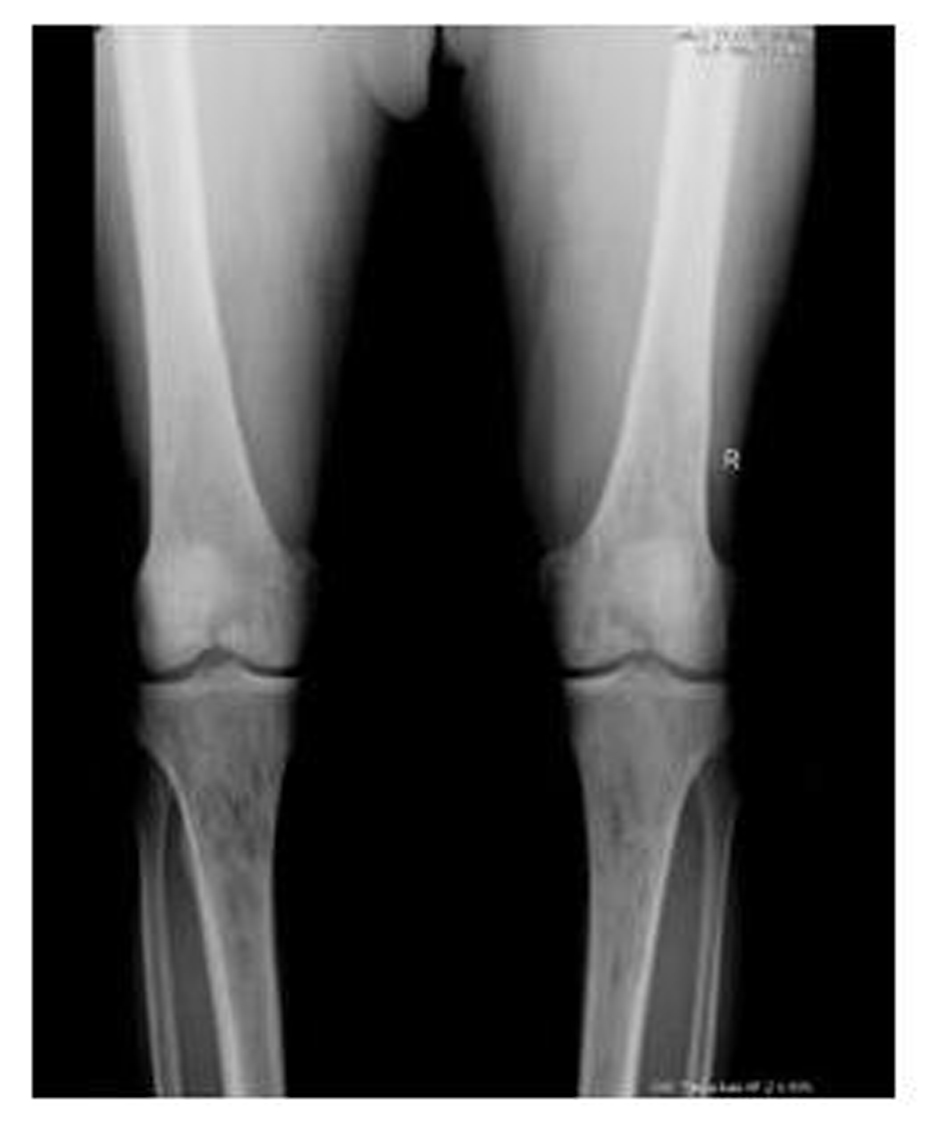

A 62-year-old male patient with knee pain, fatigue, night sweats and was admitted to our clinic. In patient history, central diabetes insipidus was diagnosed 3 months ago by nephrology clinic and vasopressin treatment was started. In laboratory examination, leukocyte counts 8.600/µL, hemoglobin level 12.6 g/dL, mean corpuscular volume 75 fL, platelet count 466.000/µL, blood urea nitrogen 8 mg/dL, creatinine 0.7 mg/dL, total protein 6.2 g/dL, albumin 2.8 g/dL, lactate dehydrogenase 184 U/L, sodium: 142 mmol/L, potassium 4.3 mmol/L, sedimentation 31 mm/h, C-reactive protein 6.17 mg/dL, thyroid stimulating hormone 2.1 µIU/mL. Peripheral blood revealed 65% neutrophils, 30% lymphocytes, 5% monocytes, cluster-platelet aggregates and normal red blood cell morphology. Immunoglobulin levels and immune fixation electrophoresis test were normal. Tomography of the abdomen and thorax was normal. Bone marrow examination was normocellular and no neoplastic infiltration. Jac-2, BCR-ABL were negative and karyotype was normal. Lytic lesions were detected in lower extremity radiographs (Fig. 1). Imaging signal changes were detected in bilateral distal part of the femur and proximal of tibia with by magnetic resonance (Fig. 2). Increased osteoblastic activity was detected in bilateral proximal and distal tibia by whole-body bone scintigraphy (Fig. 3). Biopsies were taken from tibia and was reported Langerhans cell histiocytosis (CD 1a (+), CD68 (+), Langerin (+), S-100 fokal (+)). Vinblastine 6 mg/m2 (6 weeks, 1 time per week), prednisolone 40 mg/m2/day (every day for 4 weeks) therapy was started. Zoledronic acid 4 mg/day treatment was started as once a month. After vinblastine, prednisolone therapy, patient was evaluated for response and progression was detected. Cladribine 0.14 mg/kg/day (for 5 days, 28 days) treatment was designed for 6 cure, 6 cure cladribine treatment was completed and patient was evaluated with knee MRI and whole-body bone scintigraphy again. These imaging techniques performed continuous regression.

![]() Click for large image | Figure 1. Radiolucent and osteolytic lesions with irregular margins were seen in bone structures of both knee joint’s epiphysis, metaphysis and diaphysis. |

Bone involvement identifies in the most of patients with LCH. The patient may complain of pain in a localized area of bone and a raised, soft, tender spot are detected in examination. Radiologic studies typically demonstrate a lytic, “punched out” appearance. Soft tissue mass sometimes accompanies to lytic lesion. In a study, jaw (30 percent), skull (21 percent), vertebra (13 percent), pelvis (13 percent), extremity (17 percent), and rib (6 percent) were primary sites of bone involvement in adults [1]. Our patient admitted our clinic with knee pain. Lytic lesions were detected in lower extremity radiographs. Imaging signal changes were detected in bilateral distal part of the femur and proximal of tibia with by magnetic resonance and whole-body bone scintigraphy revealed increased osteoblastic activity in bilateral proximal and distal tibia. We thought multiple myelom as differential diagnosis, but immunoglobulin levels, immune fixation electrophoresis test were normal and there was no increased plasma cell in bone marrow examination.